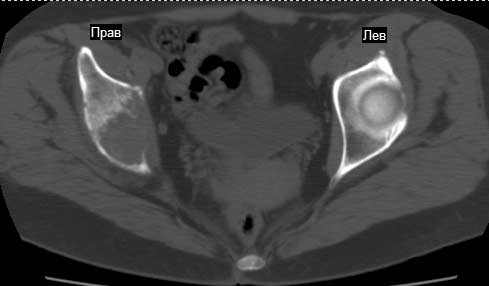

Сохранная по соматической патологии женщина ,47 лет. В 1996 г. установлен диагноз- cr левой молочной железы Т2N1Mo (2б)- проведено комплексное лечение- мастэктомия по Холстеду, ДГТ, 5 курсов ПХТ по схеме CMF. Сейчас менопауза уже 6-7 лет. В декабре 2004 года на профилактической остеосцинтиграфии с Тс99- выявлен единичный очаг повышенной фиксации препарата в зоне правой седалищной кости, рекомендована Рентгенография костей таза, выполнена- без патологии. УЗИ брюшной полости и Р-графия легких от конца апреля 2005 года - без патологии. Приблизительно 3 месяца назад появился болевой синдром в правом т/бедренном суставе с тенденцией к усилению. На рентгенограмме таза от мая 2005 года по заключению Рентгенолога очагов остеодеструкции не выявлено. Сегодня сделал ей Кт костей таза (картинки в приложении)- очаг деструкции в правой седалищной кости в зоне крыши вертлужной впадины. Что можно и нужно сделать? Жду советов, мнений, предложений по дальнейшей тактике ведения больной. С уважением, Корнев А.В.